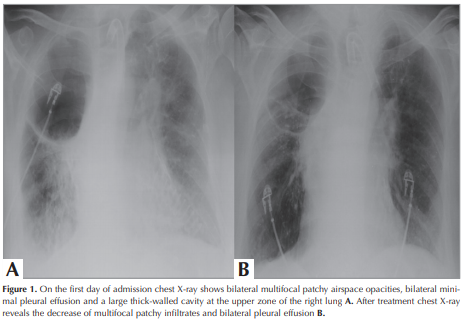

The patient was admitted to the hospital with shortness of breath, fever, and increased tracheal secretions for the last two weeks. The patient had neither traveled outside of Turkey nor had been exposed to anyone with suspected or confirmed diagnosis of COVID-19. Physical examination was remarkable for ronchi bilaterally. Heart sounds were normal. His vital signs included a temperature of 37.8°C, blood pressure of 110/75 mmHg, heart rate of 87/minute, respiratory rate of 21/minute, saturation of 90% on MV with SIMV mode and FiO2 50%. Laboratory results were as follows; white blood cell count (WBC) of 15.02x109/L, a hemoglobin (Hb) level of 11.6 g/dL, a lymphocyte count of 0.21 x109/L, and a platelet count of 203x109/L. A large cavity at upper zone of the right lung and heterogenous opacities at middle and lower zones of the both lungs were seen on chest X-ray (Figure 1 A). Chest CT showed bilateral peripheral multifocal rounded consolidation and ground glass opacities (GGO) and tree in bud opacities with centrilobular nodules. Also there was a cavity at lateral basal segment of the right lower lobe The peripheral and multifocal rounded consolidation and GGO are the typical findings of COVID-19 pneumonia. The other findings are atypical for COVID-19 pneumonia and point to a bacterial, mycobacterial or viral infection other than COVID-19 pneumonia (Figure 2). Parenteral antibiotic treatment was initiated empirically. SARS-CoV-2 RT-PCR analysis of two consecutive combined NP/OP swabs was reported negative. Even though RT-PCR results were negative twice, the patient was considered compatible with COVID-19 pneumonia with radiological and clinical features. Therefore; he was accepted to the intensive care unit (ICU) and isolated. Rapidly; hydroxychloroquine 200 mg b.i.d. and azithromycin 500 mg q.i.d were initiated for probable COVID-19 and piperacillin/tazobactam were started empirically owing to a probable bacterial co-infection. By the tracheostomy cannula, mechanical ventilation was continued. Subcutaneous low molecular weight heparin (LMWH, enoxaparin) 6000 U b.i.d was applied. After two days, he deteriorated clinically. He had subfebrile fever, tachypnea and was hypotensive with need of vasopressors. CRP and procalcitonin levels had increased, so ETA bacterial culture and viral PCR examinations were repeated. Antibiotic regimen was escalated, meropenem treatment was initiated. Pseudomonas aeroginosa ˃105 CFU/mL was cultured on microbiological examination. SARS-CoV-2 RT-PCR analysis of the ETA sample was also found to be positive. After PCR positivity, favipravir 1600 mg was administered orally twice daily on day 1, then 600 mg orally twice daily. Hydroxychloroquine, azithromycin and favipravir therapy was continued for five days. Seven days later, the patient had fever and was worsened clinically, despite suitable antimicrobial treatment for bacterial infection. CRP and procalcitonin levels increased to 250 mg/L and 32 ng/mL, respectively. Bacterial culture and RT-PCR test for SARS-CoV-2 from ETA were repeated. Bacteriological culture revealed the growth of ˃105 CFU/mL Acinetobacter baumannii, while colony count of Pseudomonas aeroginosa was decreased to <104 CFU/ml. So, intravenous colistin 300 mg was administered once daily on day 1, then 150 mg twice daily and intravenous phosphomycine 6 gr was added three times daily. Nearly three days later, the patient’s fever dropped to normal levels, and FiO2 level was reduced to 30%. Under the ongoing antibiotic regimen, the patient’s clinical and radiological findings were stable. On the 27th day, regression of lesions was observed on chest X-ray (Figure 1 B).

Figure 1